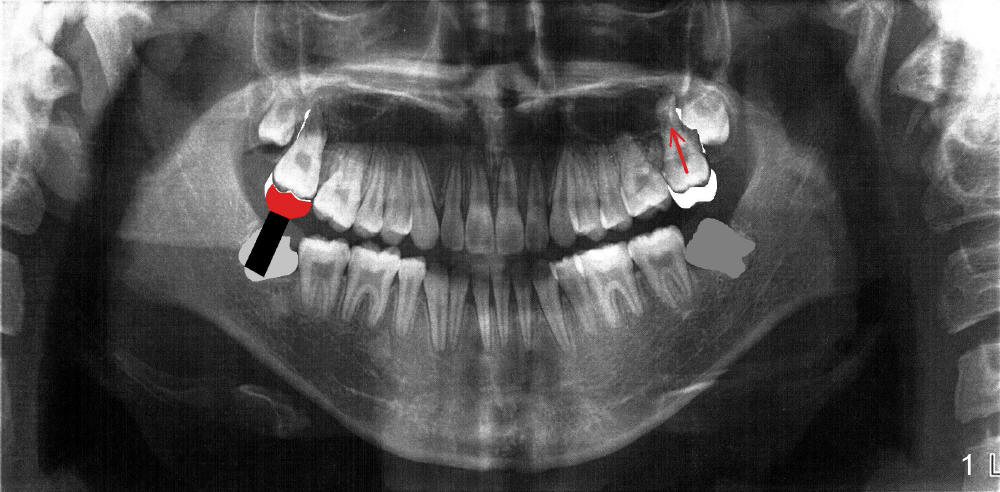

现在下颌智齿已经拔除(图一灰色部分),最简单方法是拔除上颌第二磨牙,如果今后上颌第一磨牙坏了,咀嚼可能成为问题。麻烦方法:使用微型植牙让上颌第二磨牙向根尖移位(图一箭头,intrusion),直到上颌后牙咬合面连线形成明显Curve

of

Spee,并且固定维持在原位,可能需要保留微型植牙直到完成下一步治疗。等病人十八岁时,在下颌第三磨牙处植牙(图一黑色部分),估计那里近远中距离足够植牙,因为病人下颌骨特别发育好。不过垂直距离可能是个大问题,那里损伤下牙槽神经可要成为头版头条新闻。装基牙和牙冠(红色)估计也有难度。昨天我壮着胆子打电话给口矫医生(只见一面),他好像很明白,同意重新治疗(简化)。今天他部下打电话说医生要求我出去吃饭,回答:不如再请医生来我们诊所做讲座:那种病例适合做Invisalign,那种适合traditional